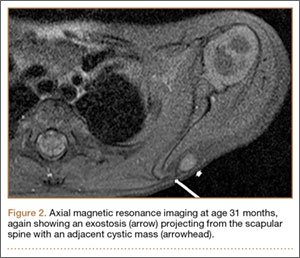

A 12-month-old boy presented to our clinic with the complaint of a mass over the left scapula. The mass was first noted incidentally several weeks earlier during bathing. Examination revealed a firm, subcutaneous, nontender mass measuring 1×2 cm located over the spine of the scapula. There were no overlying skin changes, and there was normal function of the ipsilateral upper extremity. Anteroposterior and lateral chest radiographs revealed no abnormality. Magnetic resonance imaging (MRI) showed an exostosis projecting from the scapular spine measuring 2×6×7 mm with an adjacent cystic mass measuring 5×8×9 mm that was thought to represent bursitis (Figure 1). The decision was made to observe the mass.